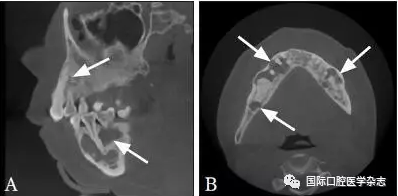

典型病例6 患者的CBCT圖像顯示上下頜骨多發(fā)性的低密度透射區(qū),但牙根完整,未見明顯吸收,牙齒仍有活力(圖6)。

A:矢狀位;B:水平位。

圖 6 骨結(jié)構(gòu)不良的CBCT圖像

Fig 6 CBCT of osseous dysplasia